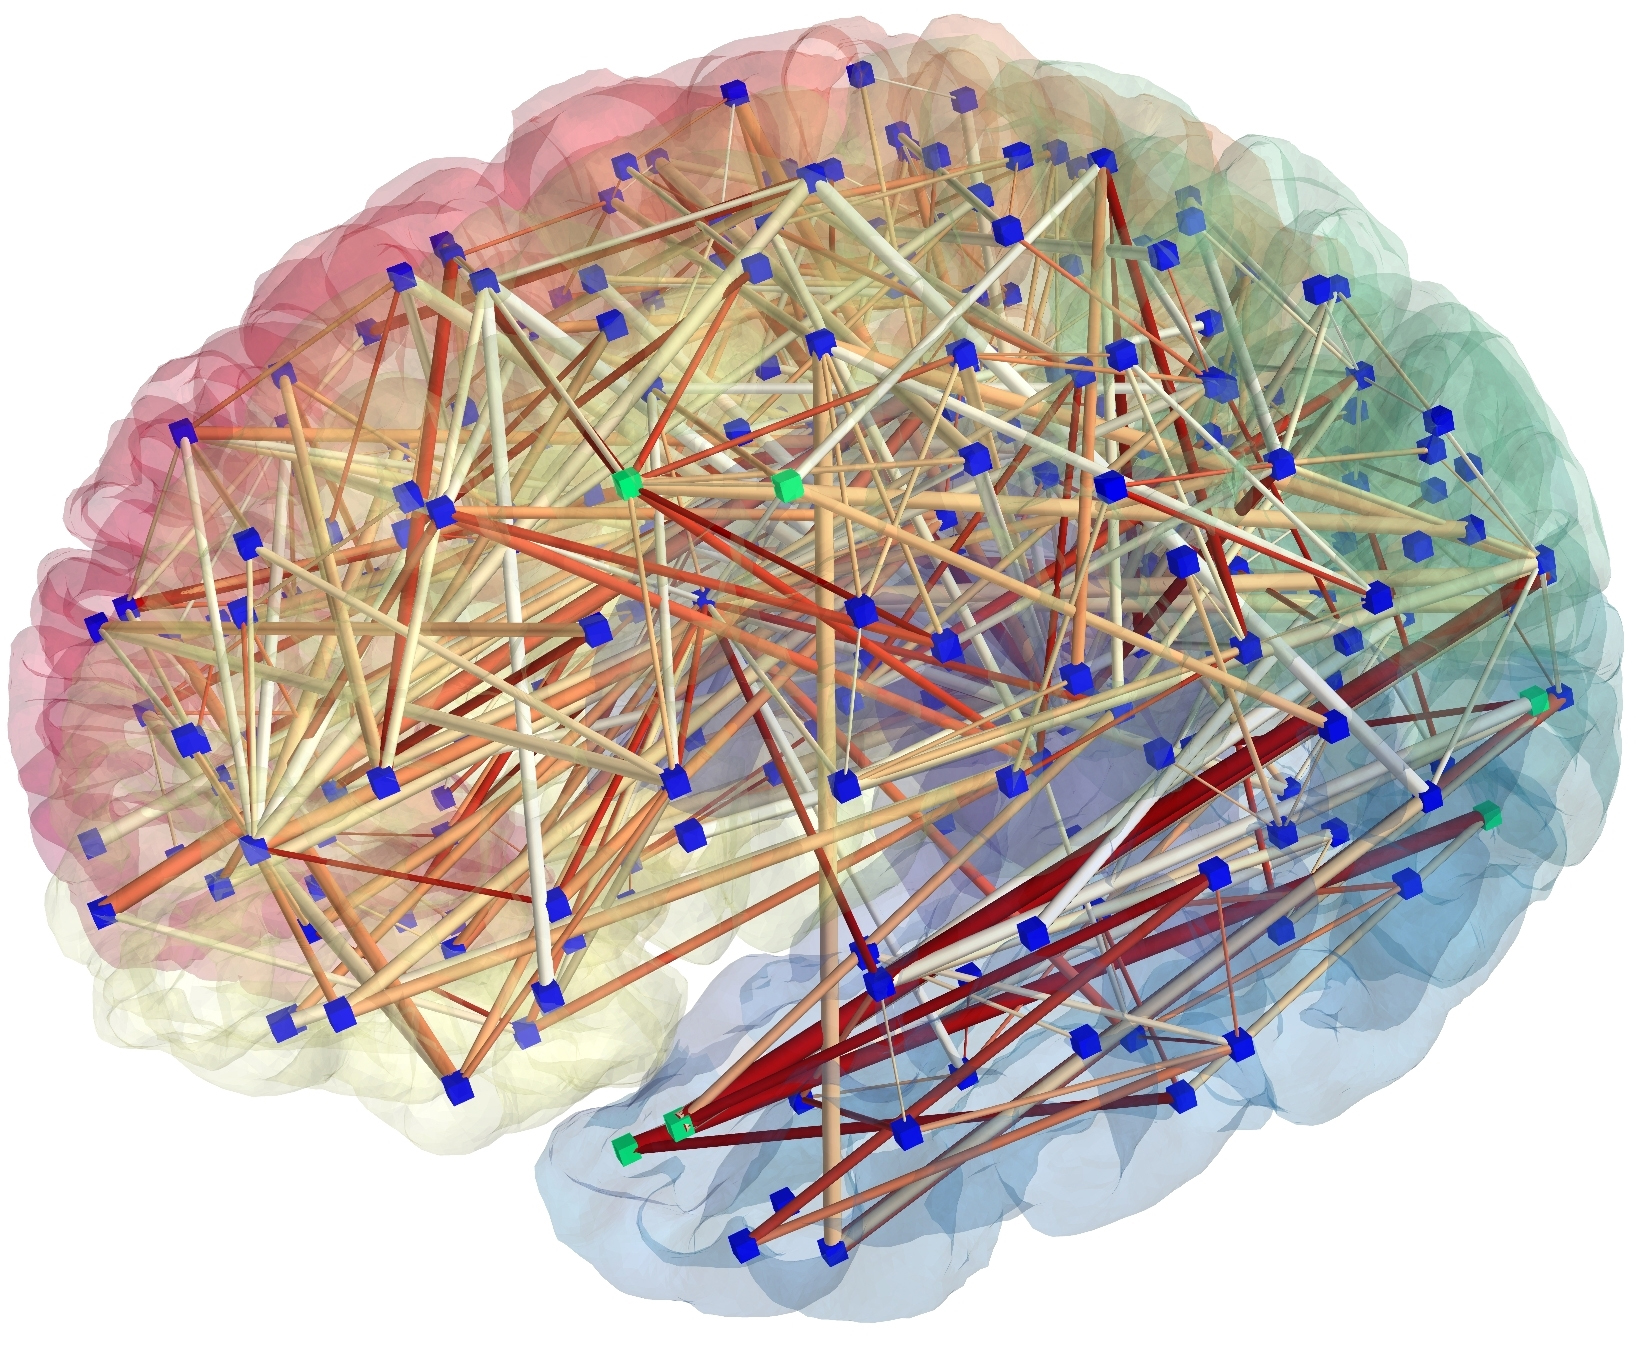

Коннектом мозга: визуализация связей и нейронных путей